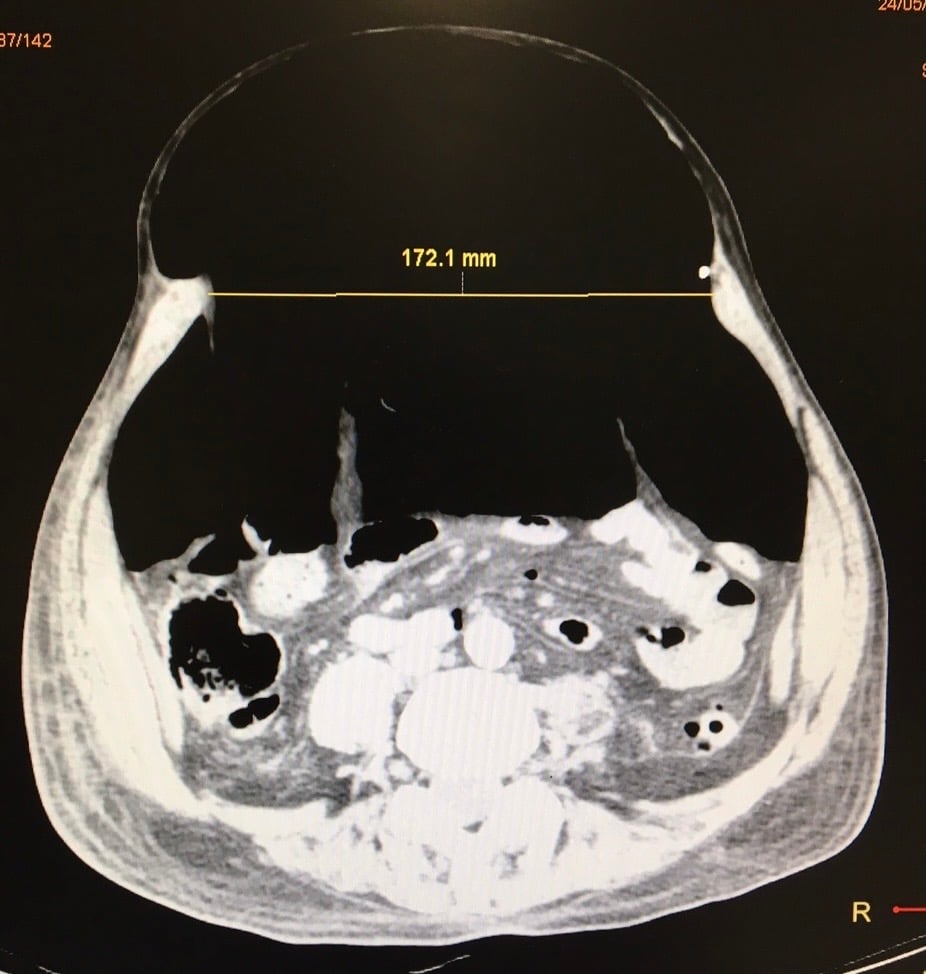

Insuflación Progresiva - Técnica Preoperatoria

Insuflación Progresiva

Técnica preoperatoria de neumoperitoneo progresivo que prepara la cavidad abdominal para facilitar el cierre de hernias complejas con contenido importante.

Características:

• Insuflación gradual de aire en el abdomen

• Expansión progresiva de la cavidad abdominal

• Reduce el riesgo de síndrome compartimental

• Mejora la adaptación respiratoria postoperatoria

Indicada para: Hernias con pérdida de dominio, hernias gigantes crónicas, eventración masiva